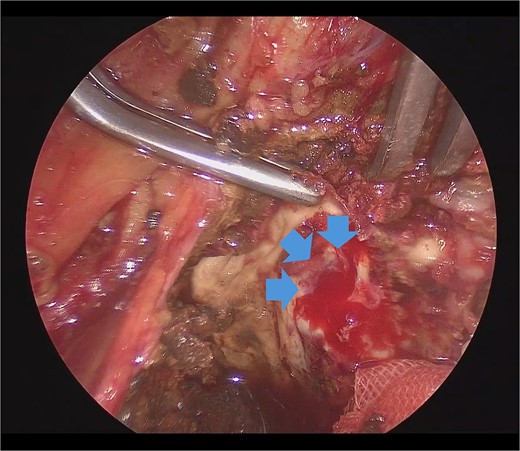

She underwent surgery under general anesthesia. A midline abdominal incision and an intraperitoneal approach were employed. The retroperitoneal space was accessed from the lateral side of the sigmoid colon to reach the CIA. The aneurysm was incised midway. The hematoma and coils were removed, and the stent graft was observed. The laparoscope was utilized to inspect areas obscured from direct view, such as behind the stent graft, to confirm that no type I or IIIb endoleak was present (Fig. 5). A type II endoleak was observed near the proximal neck of the stent graft, which was thought to be the cause of the aneurysm expansion. The IIAA was sutured with 3–0 monofilament, and the aneurysm was closed. The left ureter was close, and care was taken during suturing to avoid including it in the stitches. The operation took 177 min, and the patient was discharged on the tenth day postoperation. Follow-up CT at 7 months postoperation showed a reduction in aneurysm size (Fig. 6).

Laparoscopic view of checking for type I endoleak presence. SG, stent graft.